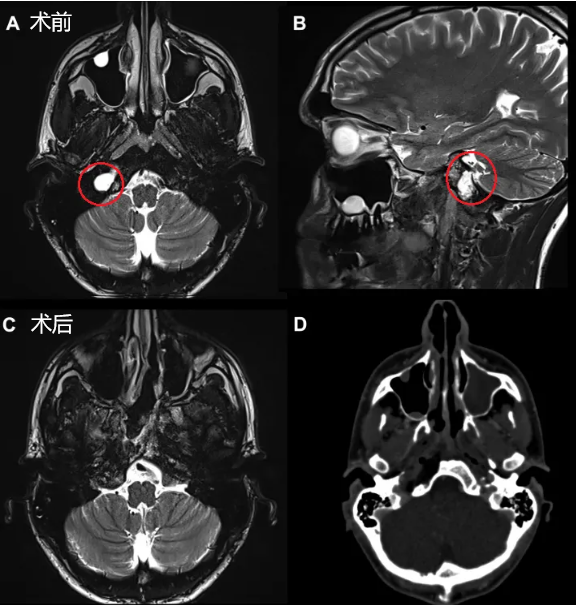

肿瘤位于颈静脉孔区,手术难度再次升级。术后很容易发生严重的并发症,致残或致死,然而,专业的颅底神经外科医生很少,Lucas 多次被告知切除困难,直至他找到了福教授。

一双“筷子”,重量大却需要用“非惯用手”单手操作,如同一个右撇子必须用左手夹黄豆,极其考验医生的“巧劲”和技术。但它却被福教授运用得炉火纯青,最终成功全切 Lucas 的肿瘤,颈静脉孔保留通畅,并通过对鼻甲粘膜的闭合有效避免了内镜手术后可能出现的脑脊液漏等并发症,极大程度上提高了 Lucas 的预后质量。

在这台手术中,“筷子技术”有助于有效地暴露、探查神经和斜坡旁的颈内动脉,并通过有限且定制的手术入路向下到达颈静脉孔区。